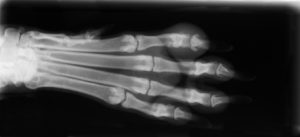

At Forever Friends Pet Care Center and Hospital in Grafton, Ohio we are proud to be on the cutting edge of medical technology. Radiology is a technique and diagnostic tool that we use to look inside the body in a completely non-invasive way. X-Rays allow us to create images of all the body’s organs.

In other words, the use of radiology gives us a view of the internal organs in your pet’s body that we otherwise could not see. It’s an important diagnostic tool that helps veterinarians detect and prevent illness.